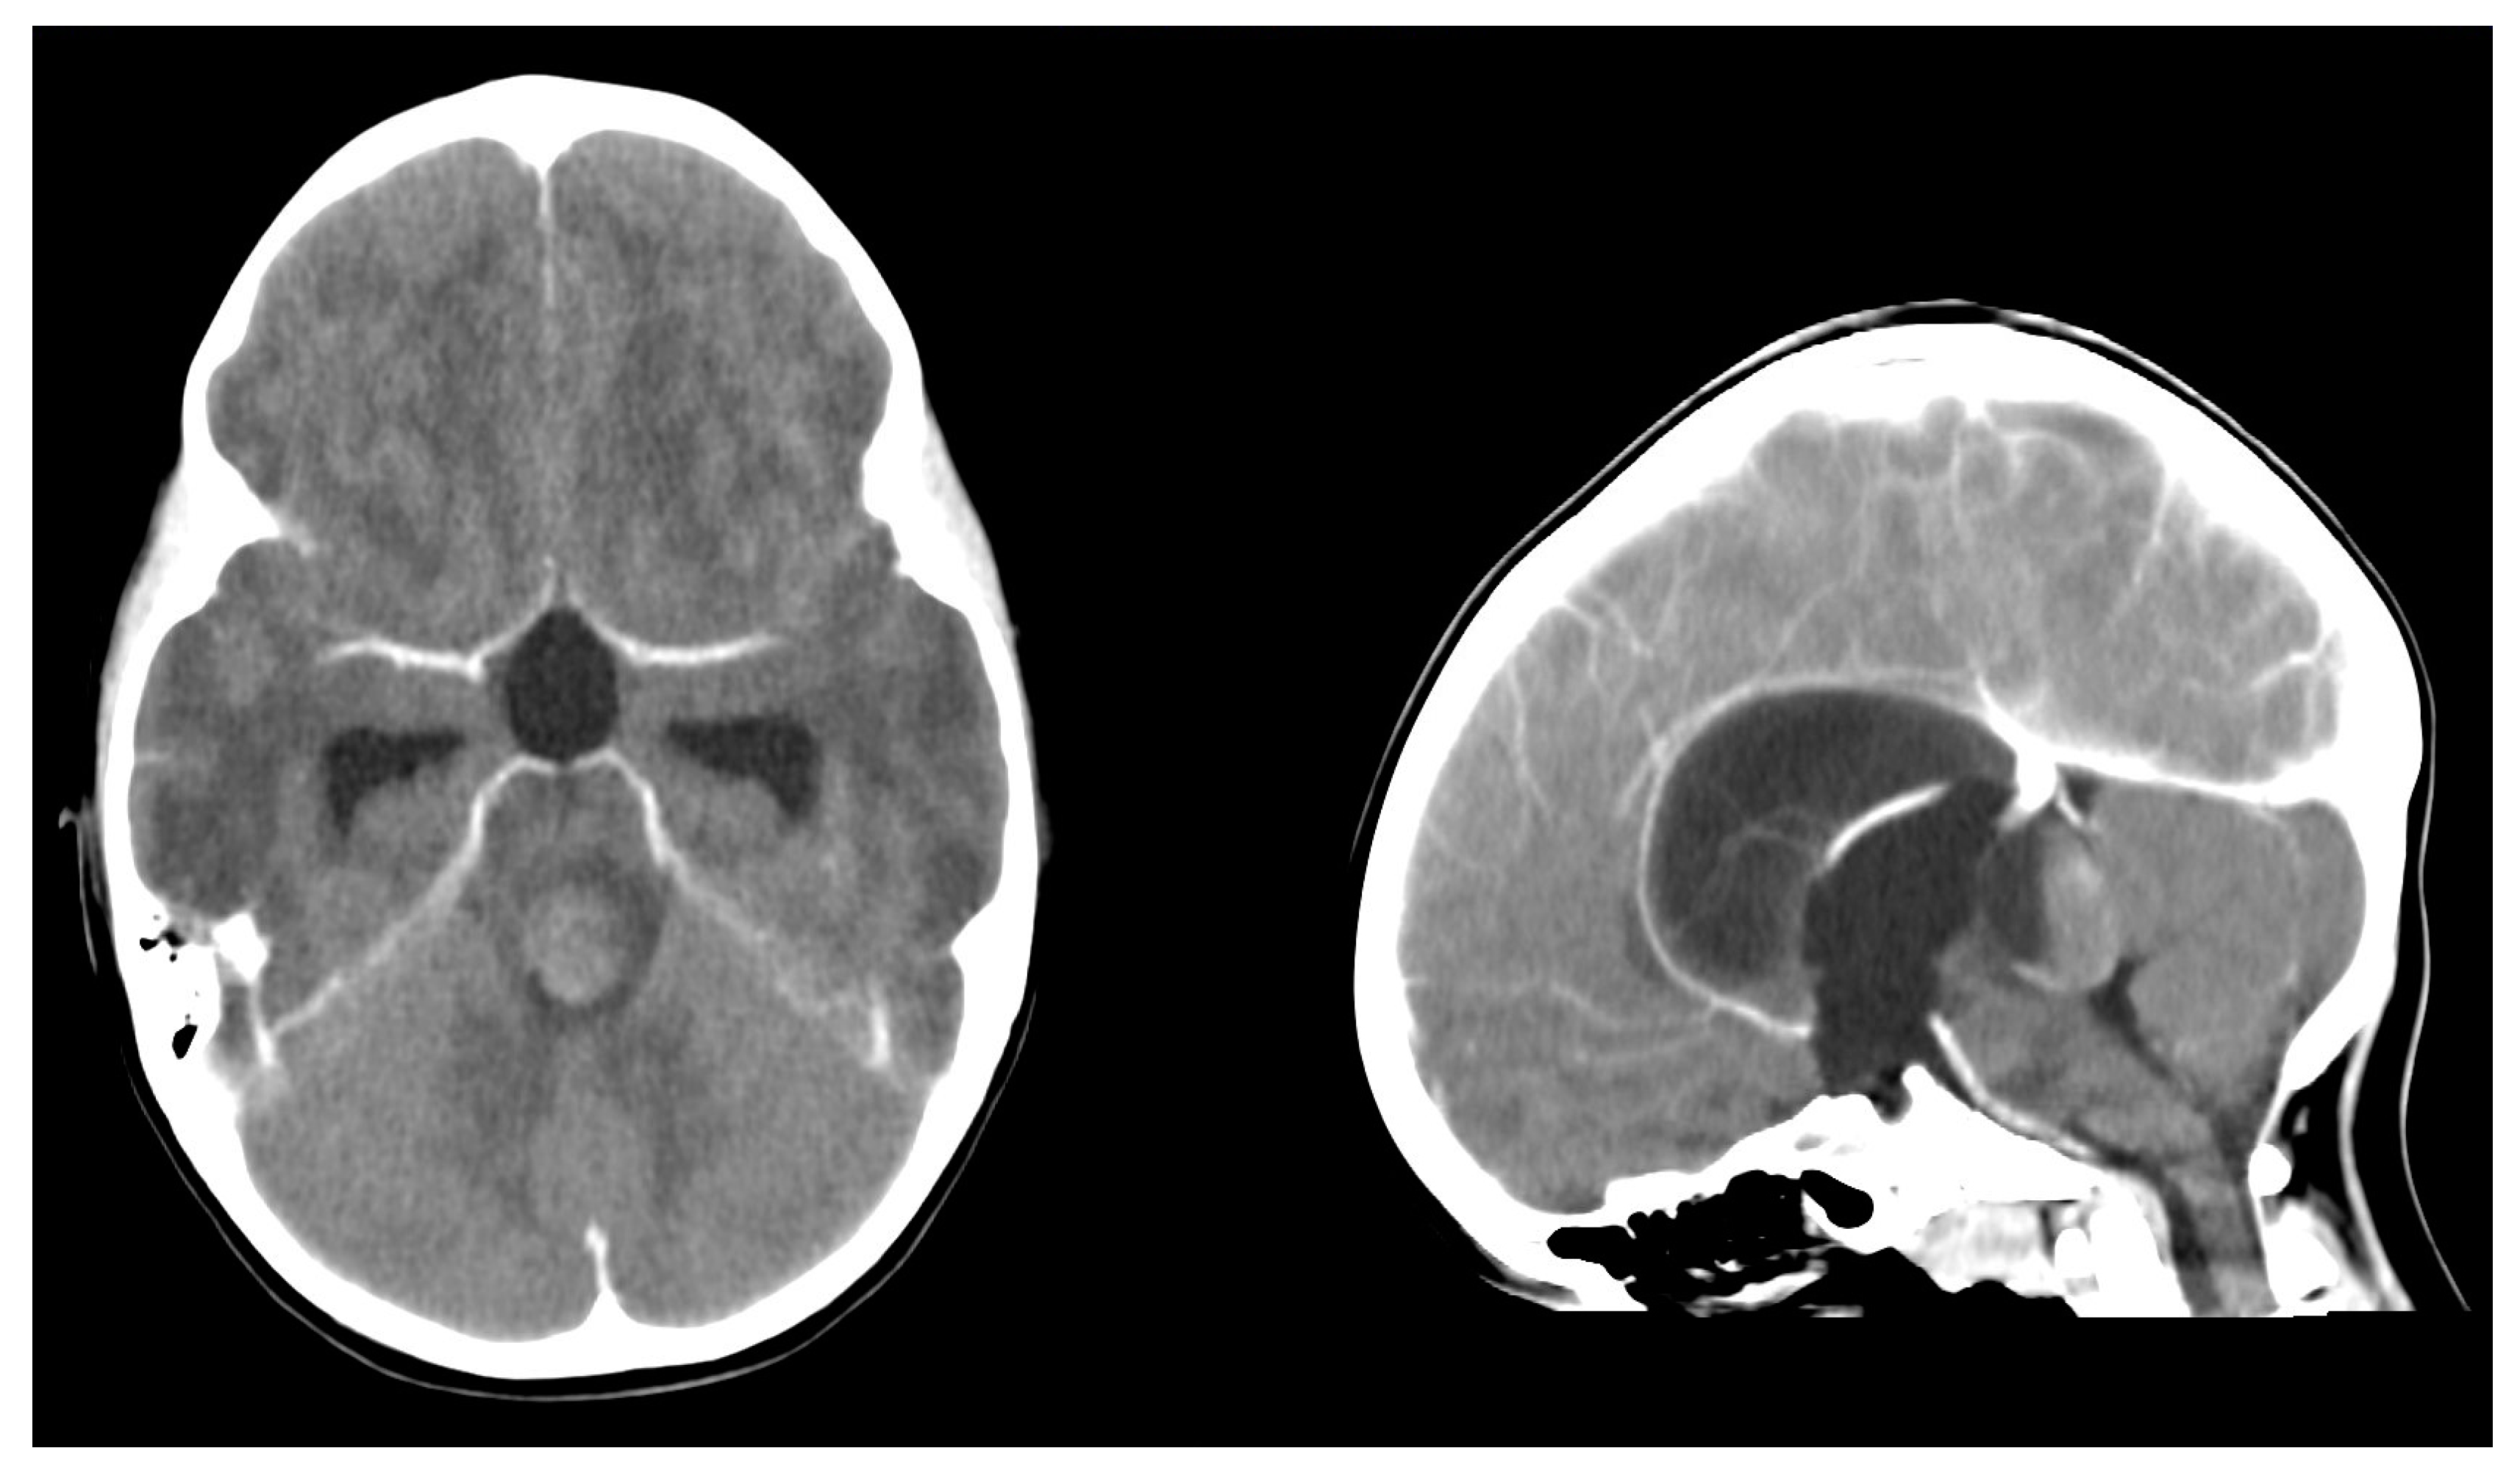

2. Case Description